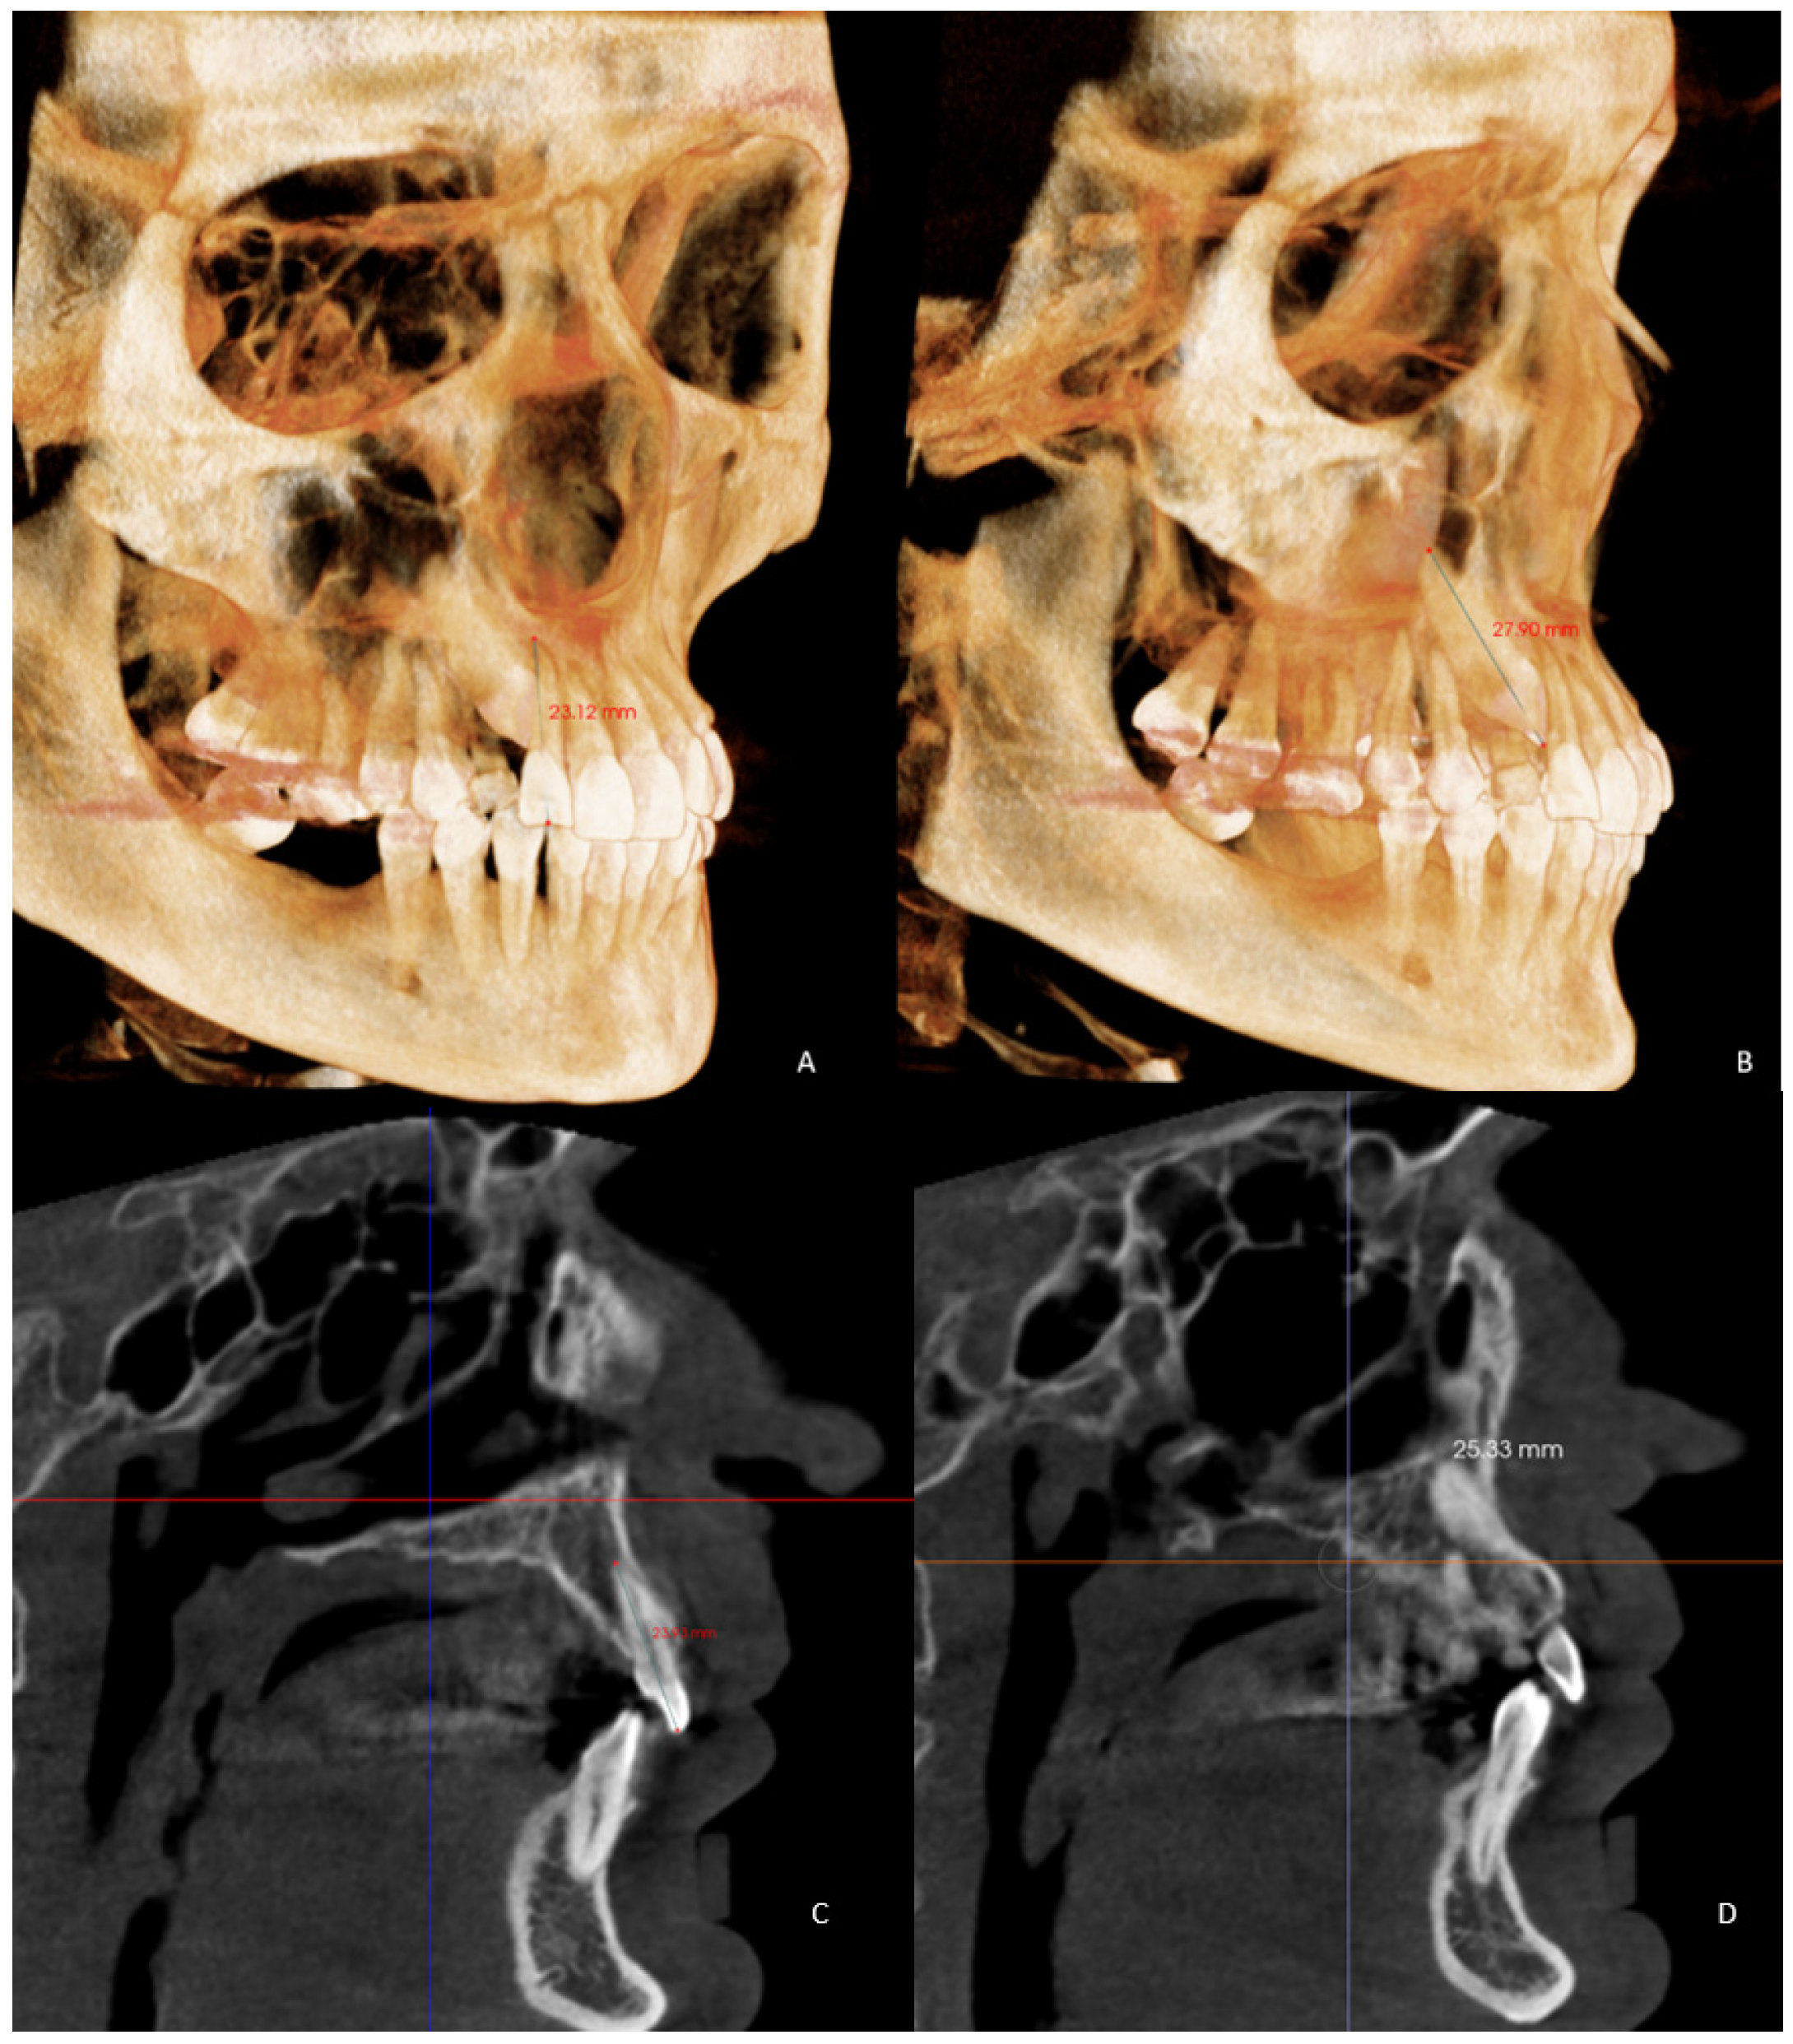

- Maxillary alveolar crest height (ACH) was measured from a tangent to the floor of the nasal fossa, to the lowest alveolar crest between both central incisors (Figure 2) in the GC and GI and, in the GI-R and GI-L, the alveolar crest height from a tangent to the floor of the nasal fossa, to the lowest alveolar crest of the canines, and in its absence, to the lowest alveolar crest of the place that would correspond to the impacted canine (ACH′) [8] (Figure 2).

- Arch length (AL) from mesial of the first permanent molar on one side to mesial of the first permanent molar on the contralateral side [35] in the GI and GC. In the GI-R and GI-L, from mesial of the first permanent molar on one side to the dental midline and from the dental midline to the mesial side of the contralateral first permanent molar (AL′) was measured (Figure 5).